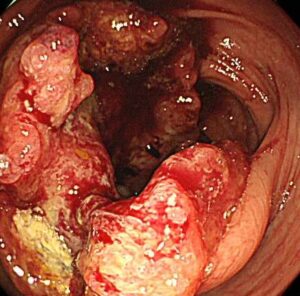

写真は、42歳男性の進行直腸がんです。

こんな感じで、早ければ20代から大腸がんが発症する症例もあります。